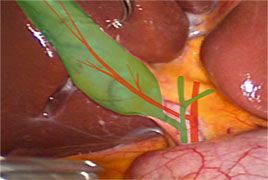

• Laparoskopische Cholezystektomie

Inhalt des Kurses ist das Erlernen der laparoskopischen Grundtechniken wie die systematische diagnostische Laparoskopie, die laparoskopische Appendektomie und Cholezystektomie sowie das laparoskopische Nähen. Der Kurs ist für Ärzte in der Facharztausbildung im Fach Allgemein- und Viszeralchirurgie vorgesehen. An dem Tübinger Trainer werden an Organkomplexen die Operationen schrittweise trainiert. Die manuellen Übungen sind in steigenden Schwierigkeitsgraden von Basistechniken bis hin zu komplexen Nahttechniken aufgebaut.

Sie werden unterstützt durch theoretische Einweisungen in die angewendeten medizinischen Instrumente, Koagulationsgeräte sowie in die Klammernahtgeräte und Knüpftechniken. Nach Abschluss des Kurses soll der Teilnehmer in der Lage sein, selbstständig unter der Assistenz eines Facharztes die laparoskopische Appendektomie und laparoskopische Cholezystektomie durchzuführen.